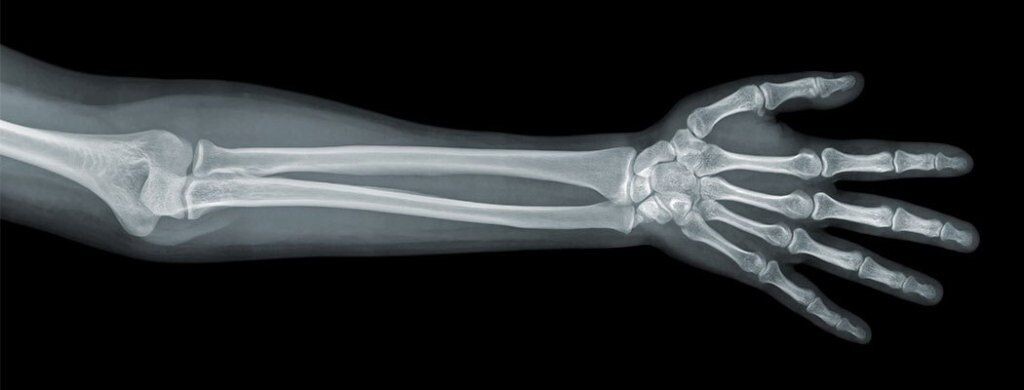

22 декабря 1895 года произошел момент, который навсегда изменил медицину. Рентген позвал жену в лабораторию для демонстрации своего открытия. Он попросил Берту положить руку на фотопластинку и включил аппарат на 15 минут.

Когда пластинку проявили, супруги увидели нечто ошеломляющее — четкие тени костей руки Берты, а на безымянном пальце — темное кольцо. Впервые в истории человек увидел собственный скелет, оставаясь живым.

"Я видела свою смерть!" — воскликнула потрясенная Берта, глядя на снимок. Эта фотография стала первым в мире рентгеновским снимком человека и одним из самых значимых научных документов в истории.

Уже в январе 1896 года врачи в Европе и Америке начали использовать рентгеновские лучи для диагностики переломов. В Вене хирург использовал рентген для обнаружения пули в руке пациента. В Лондоне с помощью новых лучей нашли иголку в руке женщины.

Несмотря на опасности, медицинская революция была необратимой. Впервые в истории врачи получили возможность заглянуть внутрь живого человека без вскрытия. Диагностика переломов, поиск инородных тел, обнаружение пневмонии — все это стало возможным благодаря рентгеновским лучам.